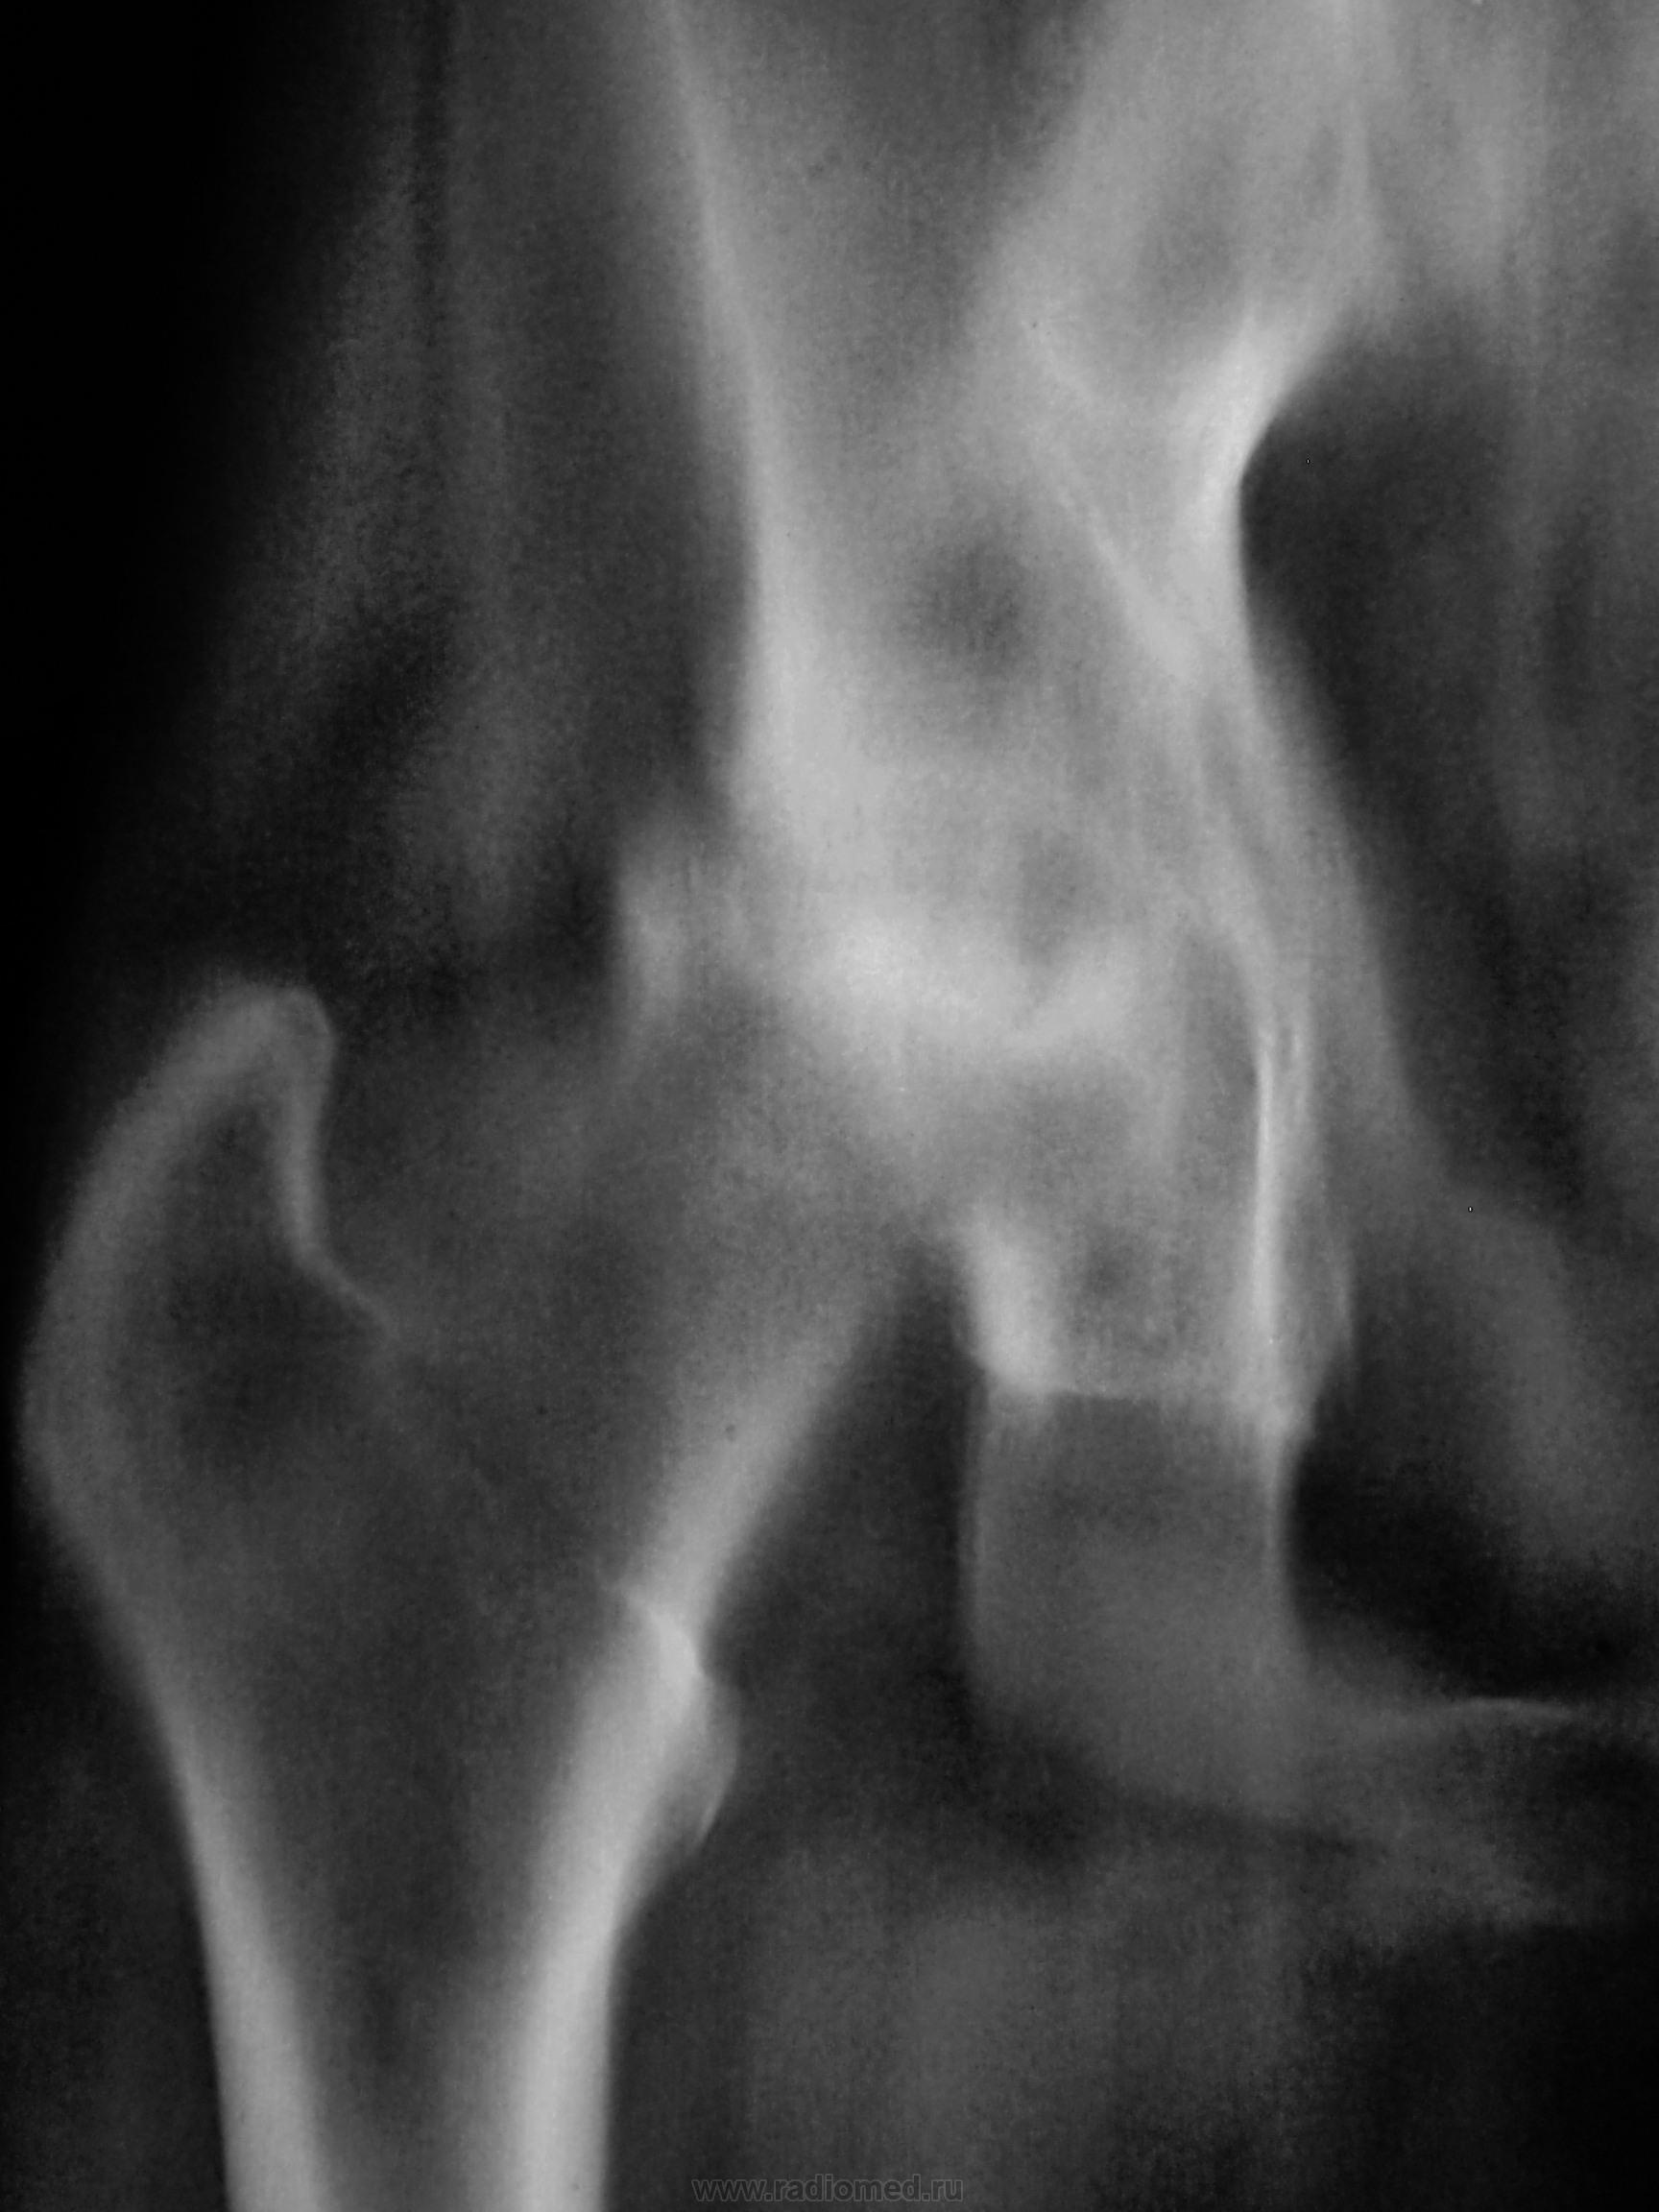

Вот и решили мы, пройтись по суставу линейной томографией, ибо согласия в товарищах не было. Конечно, линейку нельзя сравнить с КТ, но мал-мал картина прояснилась, да и консультанты, одобрительно покивали головами.

Конечно, пациентке было сделано только 4 среза, остальные иллюстрации - это происки АРМа в тесном контакте с ДИКОМОМ.

Отдельно головка.

Приложения: